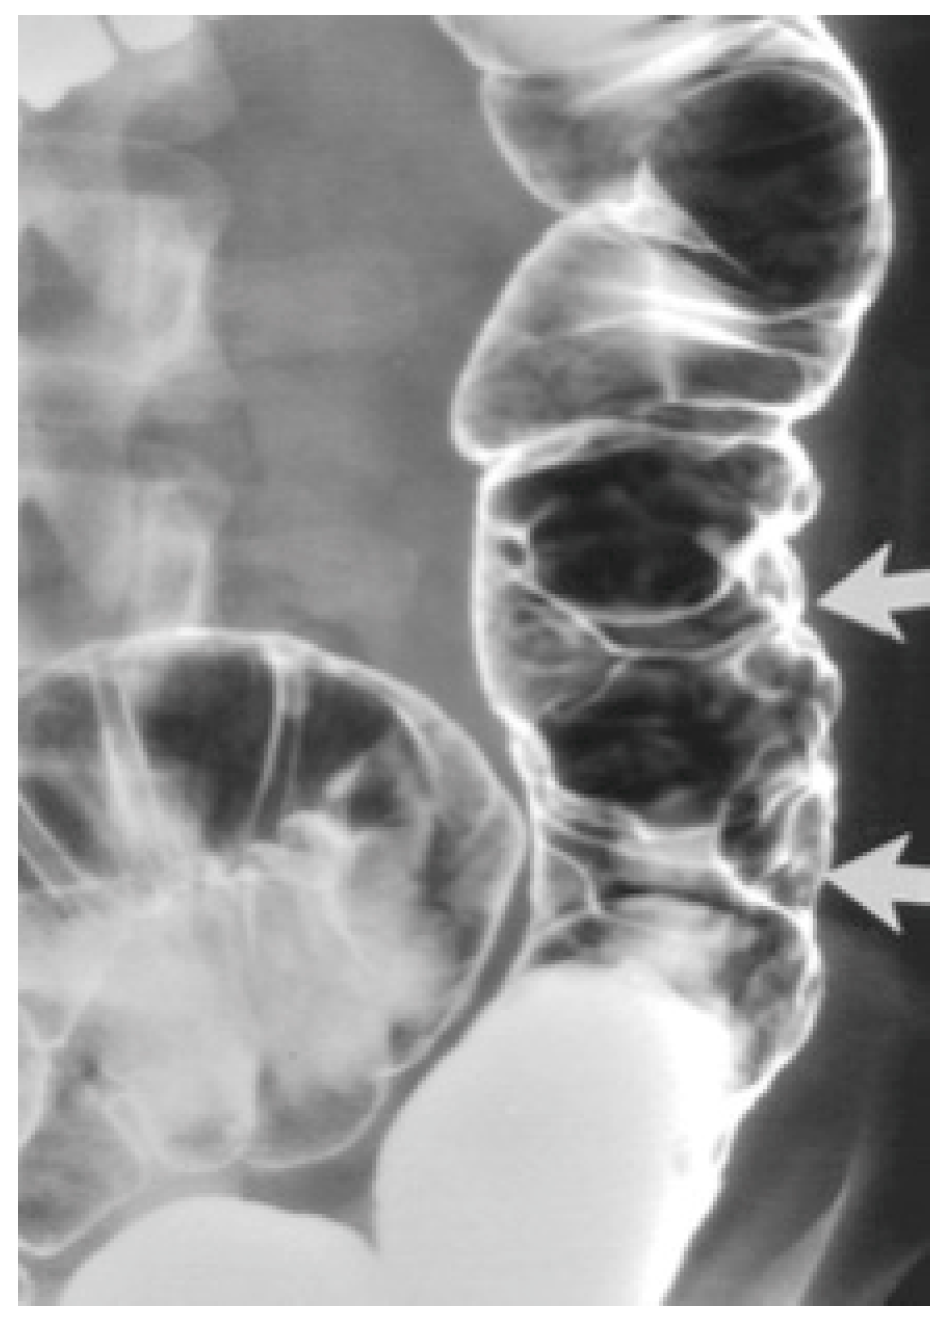

2. Detailed Case Description